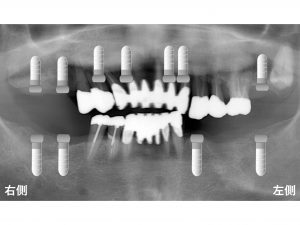

もし、全ての欠損部位に対してインプラント埋入した場合には

以下のようになりなす。

このような状態では

抜歯を最小限にして

全ての欠損に対して噛むことが可能になります。

以下のようにインプラントを埋入します。

このようなプランをご希望される患者様いらっしゃいます。